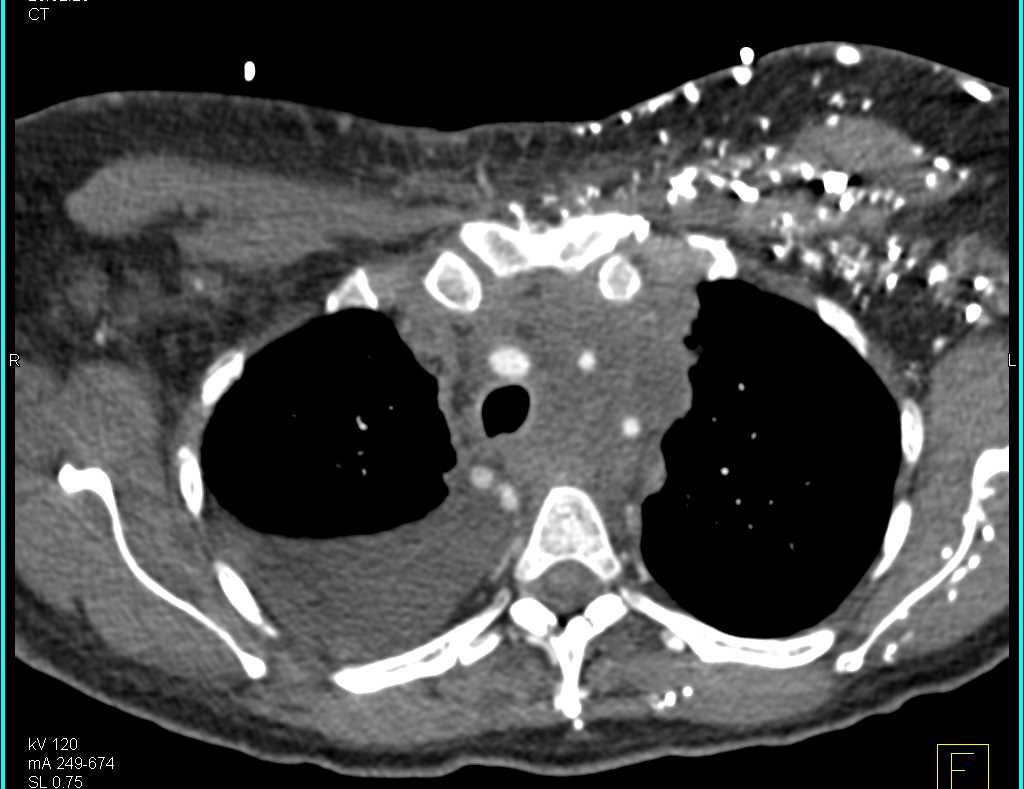

Incidental Lung Cancer in Patient Evaluation for Suspected Coronary Artery Disease